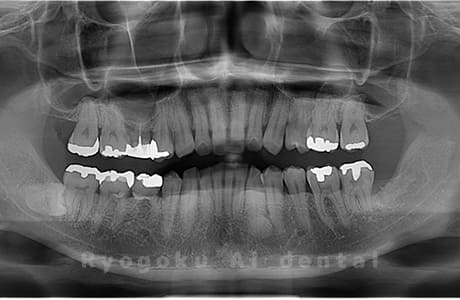

Case10

- 原因

- 下顎左の親知らず

- 治療内容

- 下顎左の親知らずを抜歯したケースです。

<リスク・副作用>

手術後は痛み、腫れ、痺れなどの副作用が生じる場合があります。